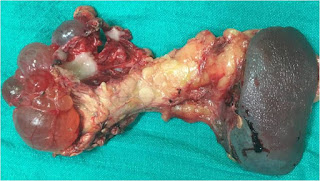

Figure D: Distal pancreatectomy + splenectomy specimen showing multiple thin walled cysts

The patient underwent laparoscopy assisted distal pancreatectomy with splenectomy. At laparoscopy there was a large (approximately 9 x 7cm) multiloculated exophytic tumor in the body and tail region of pancreas that was adherent to the mesocolon and left branch of the middle colic artery (Figure D). She had an uncomplicated postoperative period and was discharged on 8th day following surgery. Histopathology revealed cysts lined by single layer of cuboidal epithelial cells filled with clear cytoplasm.